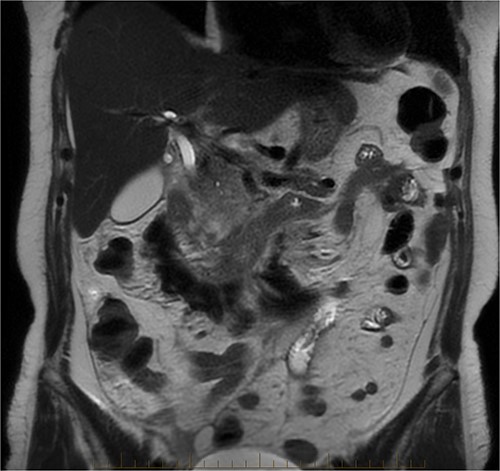

After further discussion with the reporting radiologist, a magnetic resonance imaging (MRI) was performed, which confirmed the presence of an acute periduodenal hematoma surrounding D2 and D3, lying in the retroperitoneal space, anterior to the right perirenal space. Etiology was uncertain. No abnormal enhancement within the bowel to suggest a bowel wall lesion or infiltrating mass (Figs 3 and 4).

MRI abdomen, axial view. T2 hypointense, T1 iso to hyperintense material surrounding D2/D3 without enhancement in keeping with hemorrhage. No vascular or bowel wall lesion identified.